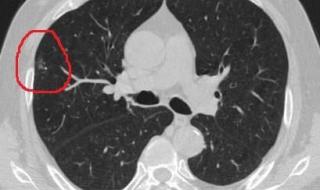

肺部多发结节不一定是癌症。多数肺部多发结节属于良性病变,尤其是边界清晰、形态规则且生长缓慢的结节。例如,炎症性结节在接受抗感染治疗后,通常可缩小甚至消失。此外,结核、肉芽肿等非癌性疾病也可能表现为肺部多发结节,这类病变一般不会发展为恶性肿瘤。恶性结节需警惕特定特征。

肺部多发性结节不一定是癌症。其性质和病因复杂,需通过进一步检查和评估明确。以下是具体分析:一、定义与分类肺部多发性结节指肺部存在两个或以上直径≤3厘米的类圆形或不规则病灶,多表现为含气囊腔样病变。根据分布范围可分为:局限性:结节局限于单侧或双侧肺部;弥漫性:结节广泛分布于全肺。

恶性因素需警惕恶性多发性肺结节主要包括两类情况:一是原发性肺癌发生肺内转移,形成多个癌性结节;二是其他部位肿瘤(如乳腺癌、结直肠癌)通过血行转移至肺部,导致多发转移灶。